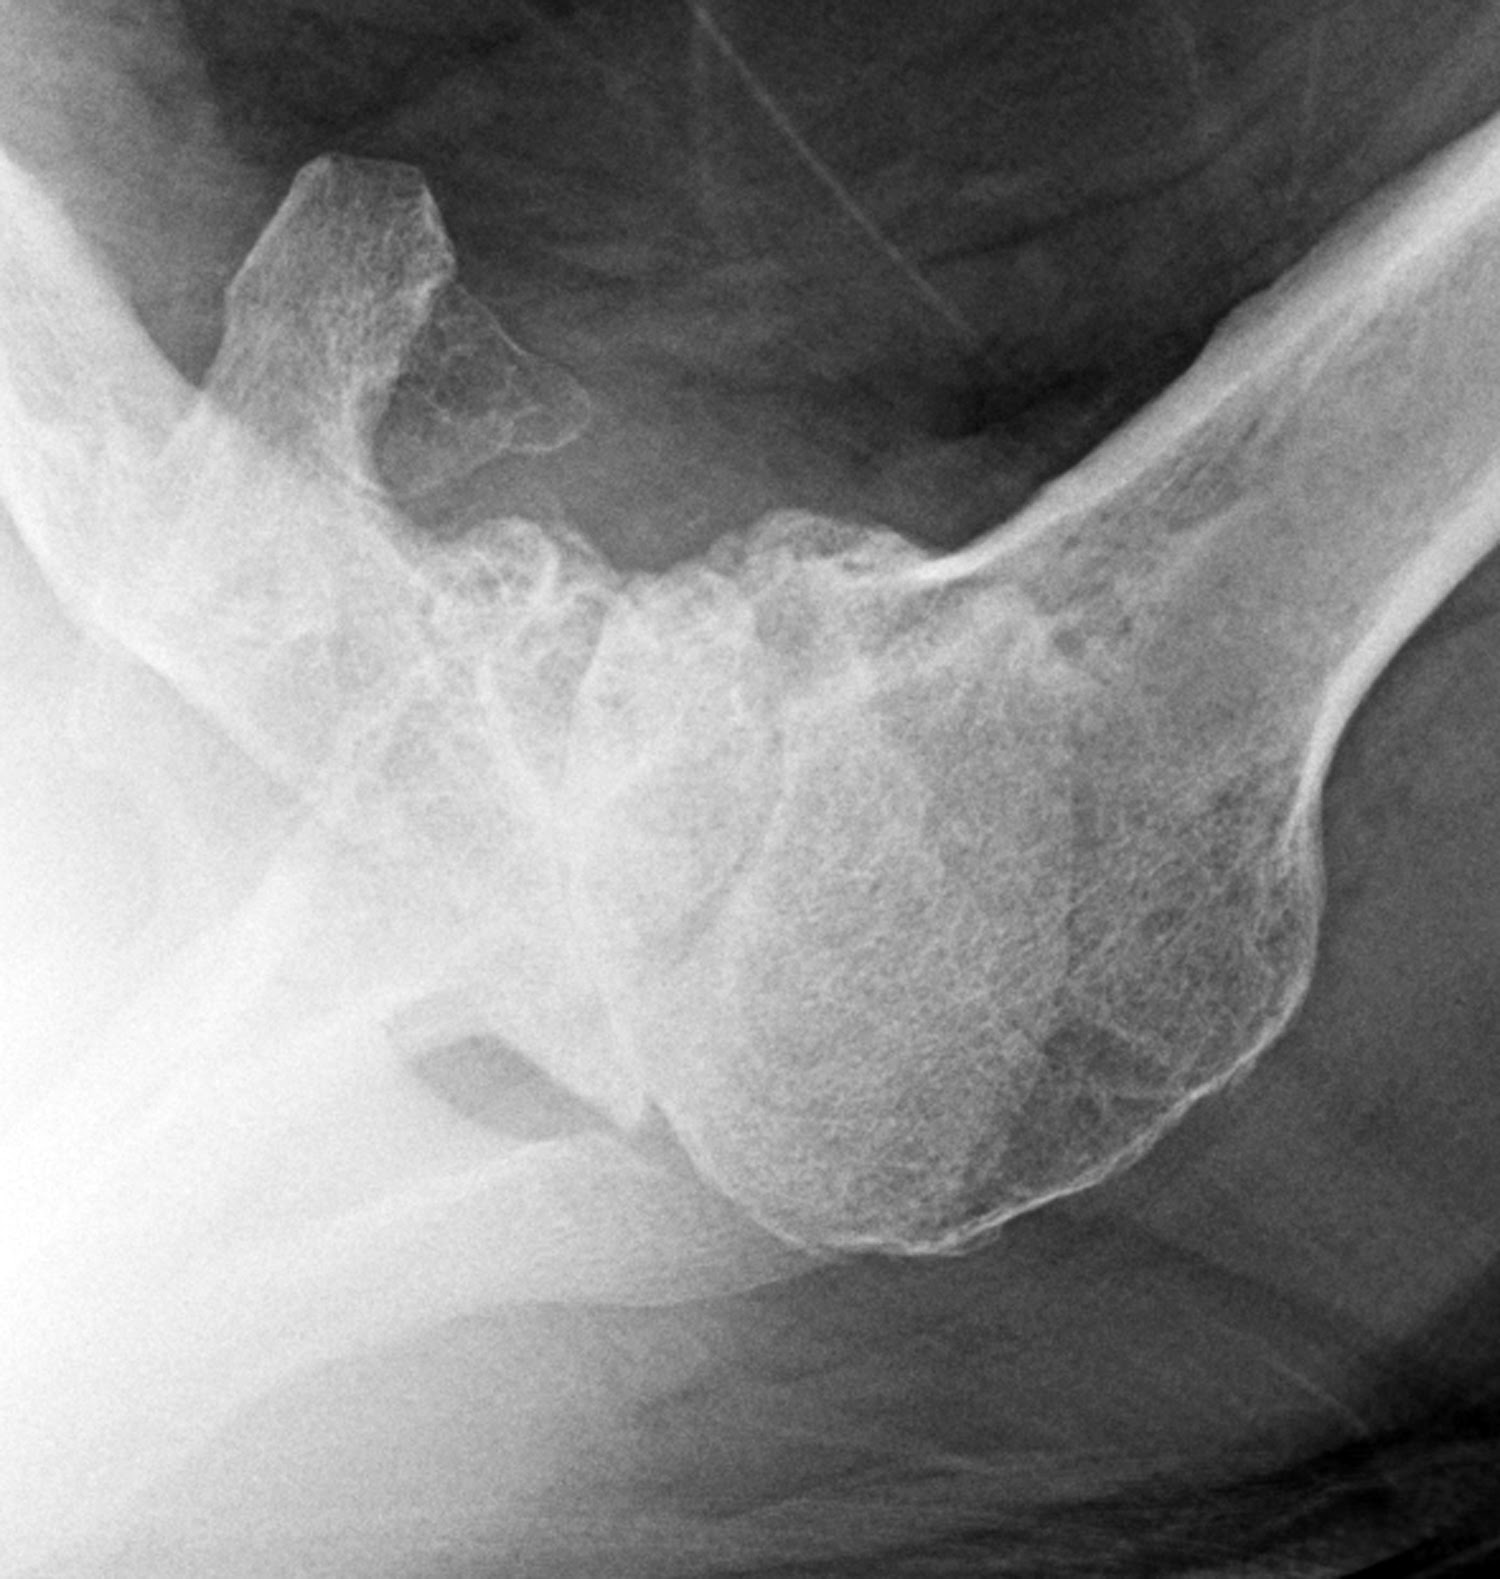

UW Shoulder and Elbow Academy How bad is the shoulder arthritis on xray? Shoulder X Ray Showing Arthritis Symptoms of shoulder arthritis may include pain in the shoulder joint, stiffness and reduced range of motion. They can help distinguish among various forms. Healthcare providers use a shoulder x. Over time, arthritis leads to cartilage loss. Shoulder arthritis is inflammation in your shoulder joint. Symptoms include pain, stiffness, decreased. Shoulder arthritis symptoms include persistent pain, stiffness, limited range of. Shoulder X Ray Showing Arthritis.

From www.researchgate.net

Shoulder Xrays taken from a patient with severe endstage arthritis Shoulder X Ray Showing Arthritis Shoulder arthritis is inflammation in your shoulder joint. Shoulder arthritis symptoms include persistent pain, stiffness, limited range of motion, weakness, and a grinding or clicking sensation in the joint, which, if left untreated, could. Symptoms include pain, stiffness, decreased. Over time, arthritis leads to cartilage loss. Healthcare providers use a shoulder x. There are many nonoperative treatments for shoulder arthritis,. Shoulder X Ray Showing Arthritis.